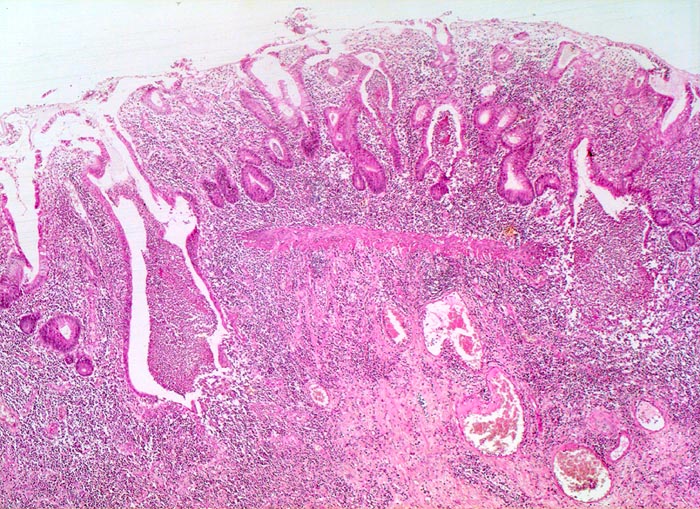

Makroskopisch finden sich häufig longitudinal ausgerichtete Ulzera mit Querverbindungen und Konfluenz. Residuelle Schleimhautinseln imponieren als Pseudopolypen. In der Remissionsphase ist die Schleimhaut glatt und blass, das Faltenrelief ist vergröbert und verstrichen und es finden sich häufig Granulationsgewebspolypen.

Mikroskopisch findet sich je nach Entzündungsaktivität eine mehr oder weniger ausgeprägte diffuse Verdichtung des lymphoplasmazellulären Entzündungsinfiltrates mit Beimischung von Granulozyten in Form einer Kryptitis oder von Kryptenabszessen. Bei einer stark aktiven Entzündung finden sich zusätzlich Erosionen und Ulzera mit Ausdehnung der Entzündung über die Mukosa hinaus in die Submukosa oder in noch tiefere Schichten bei hochflorider Kolitis. Die Kryptenarchitektur ist gestört, die Anzahl der Krypten und der Becherzellen vermindert. In der Regeneratphase finden sich zahlenmässig reduzierte und verkürzte Krpyten mit normaler Anzahl Becherzellen. Meist bleibt eine leichte Verdichtung der Entzündungszellen in der Lamina propria bestehen.

Abwechslungsweise oberflächliche Ulzera und pseudopolypöse Schleimhautvorwölbungen.

Entzündungsinfiltrate in Mukosa und Submukosa.

Unregelmässig geformte und verzweigte Krypten (Kryptenarchitekturstörung).

Krpyten enden deutlich oberhalb der Lamina muscularis mucosae (Kryptenatrophie).

Verminderte Schleimbildung und Becherzellverlust.

Basal betonte Plasmozytose und Infiltrate neutrophiler Granulozyten.

Ansammlungen neutrophiler Granulozyten in Kryptenlumina (=Kryptenabszesse) und Infiltrate von neutrophilen Granulozyten im Kryptenepithel (=Kryptitis).